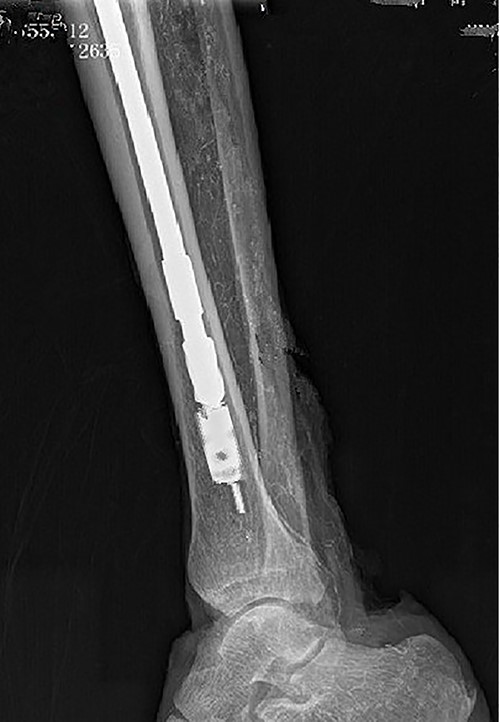

Intraoperative X-ray showing that the broken nail extractor was pulled back and the barb hooked the canal wall.